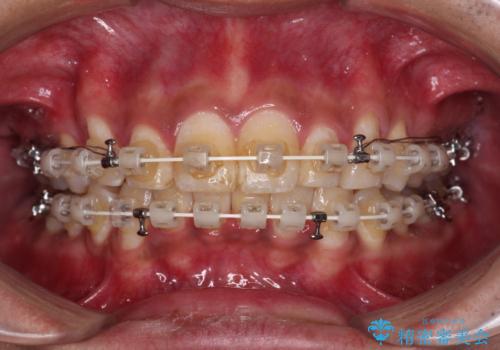

深い咬み合わせと前歯のデコボコ ワイヤー装置での抜歯矯正

- 深い咬み合わせと前歯のデコボコを改善したいとのことで来院された患者様です。

口元の突出感はないものの、上顎前歯のデコボコが著しく、右側の咬み合わせがずれていたため、上顎右側第一小臼歯1本を抜歯することとしました。

咬合力が非常に強く、抜歯したスペースがなかなか閉じないであろうことは予想できましたが、思っていた以上に期間がかかりました。

前歯のすり減りも著しかったため、仕上げの位置の調整にも期間を要しました。